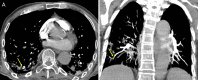

Results: The study population comprised 82 men and 19 women, with a mean age of 64.1 years ± 15.0 (95% confidence interval [CI]: 60.4, 67.6) years. CT pulmonary angiography was performed 19.8 days ± 6.1 (95% CI: 18.1, 20.2) after symptom onset and 10.5 days ± 3.8 (95% CI: 10.2, 12.9) after admission. Of 101 patients, 41 had PTE (40.6%). PTE was mostly bilateral or only right (37/41 [90.2%]), mainly involved segmental (37/41 [90.2%]) or subsegmental (25/41 [61.0%]) arteries and affected mainly the branches of the lower lobe (30/41 [73.2%]). Parenchymal segments supplied by segmental arteries with PTE showed a prevalent consolidation pattern (25/37 [67.6%]). Deep vein thrombosis was present only in five of 41 (12.2%) patients. Comparing groups with and without PTE, no significant difference was observed in age, sex, symptom onset, comorbidities, tumor history, use of respiratory supports, activated partial thromboplastin time, prothrombin time, and deep vein thrombosis. Conversely, differences were evaluated in CT lesion score (15.7 ± 1.4 [95% CI: 15.3, 16.1] vs 14.1 ± 1.1 [95% CI: 13.8, 14.4]; P = .035), d-dimer level (P < .001), lactate dehydrogenase level (P < .001), and C-reactive protein level (P = .042).

Conclusion: PTE in COVID-19 involves mainly the segmental and subsegmental arteries of segments affected by consolidations in patients with more severe lung disease. The authors hypothesize that the development of PTE in COVID-19 might be a pulmonary artery thrombosis because of severe lung inflammation and hypercoagulability rather than thromboembolism.© RSNA, 2020.